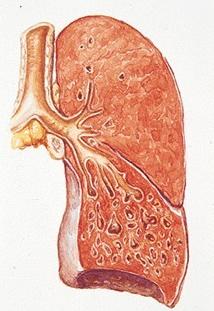

肺栓塞和下肢静脉血栓

疾病介绍:肺栓塞、肺动脉高压肺栓塞(pulmonary embolism, PE)是以各种栓子阻塞肺动脉系统为其发病原因的一组疾病或临床综合征的总称,以下肢静脉血栓脱落引起…【详细】

肺栓塞和下肢静脉血栓

疾病介绍:肺栓塞、肺动脉高压肺栓塞(pulmonary embolism, PE)是以各种栓子阻塞肺动脉系统为其发病原因的一组疾病或临床综合征的总称,以下肢静脉血栓脱落引起…【详细】

肺栓塞和下肢静脉血栓

疾病介绍:肺栓塞、肺动脉高压肺栓塞(pulmonary embolism, PE)是以各种栓子阻塞肺动脉系统为其发病原因的一组疾病或临床综合征的总称,以下肢静脉血栓脱落引起…【详细】

肺栓塞和下肢静脉血栓

疾病介绍:肺栓塞、肺动脉高压肺栓塞(pulmonary embolism, PE)是以各种栓子阻塞肺动脉系统为其发病原因的一组疾病或临床综合征的总称,以下肢静脉血栓脱落引起…【详细】

肺栓塞和下肢静脉血栓

疾病介绍:肺栓塞、肺动脉高压肺栓塞(pulmonary embolism, PE)是以各种栓子阻塞肺动脉系统为其发病原因的一组疾病或临床综合征的总称,以下肢静脉血栓脱落引起…【详细】

肺栓塞和下肢静脉血栓

疾病介绍:肺栓塞、肺动脉高压肺栓塞(pulmonary embolism, PE)是以各种栓子阻塞肺动脉系统为其发病原因的一组疾病或临床综合征的总称,以下肢静脉血栓脱落引起…【详细】

肺栓塞和下肢静脉血栓

疾病介绍:肺栓塞、肺动脉高压肺栓塞(pulmonary embolism, PE)是以各种栓子阻塞肺动脉系统为其发病原因的一组疾病或临床综合征的总称,以下肢静脉血栓脱落引起…【详细】